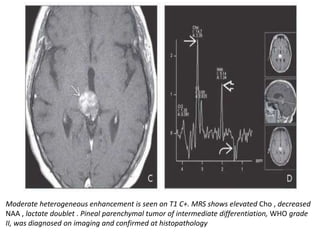

Moderate heterogeneous enhancement is seen on T1 C+. MRS shows elevated Cho , decreased

NAA , lactate doublet . Pineal parenchymal tumor of intermediate differentiation, WHO grade

II, was diagnosed on imaging and confirmed at histopathology